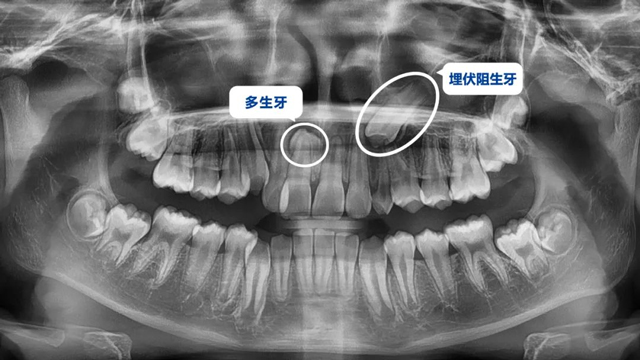

這位小患者的口腔問題包括:牙列不齊,個別門牙反頜,左上尖牙完全埋伏阻生,另外,CBCT顯示右上門牙牙根腭側內還有一顆多生牙。

簡單地說,牙齒不整齊只是小問題,他更大的問題是:在不該長牙的地方多長了一顆牙,而乳尖牙滯留,早該替換出來的尖牙長不出來,這兩顆牙的問題如果不及時干預治療,會帶來很多長期的口腔問題。

據了解,位于腭側的多生牙緊挨著已經替換完的1號恒牙(門牙),如不拔除會影響整個牙列的整齊度,后期也可能損傷1號牙的牙根,導致這顆牙齒松動甚至脫落。